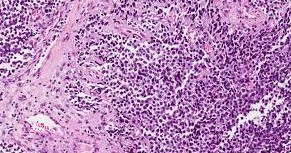

Le type le plus fréquent de RMS est le rhabdomyosarcome embryonnaire. Il représente de 50 à 70 % de tous les RMS chez l’enfant. Le RMS est le type le plus courant de sarcome des tissus mous chez l’enfant. Il apparaît rarement chez l’adulte.